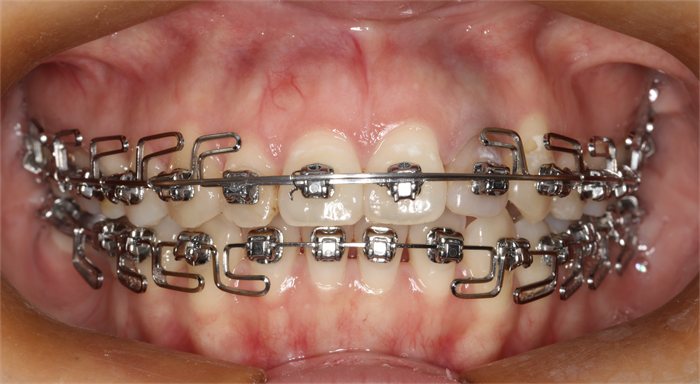

功能正畸

隱形矯治